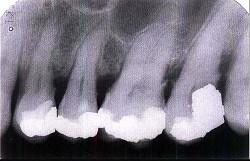

问题 牙槽骨水平型吸收的特点是()

选项 A.是最常见的吸收方式 B.牙槽间隔、唇颊侧或舌侧的嵴顶边缘呈水平吸收 C.牙槽嵴高度有明显降低 D.常形成骨上袋 E.以上均是

答案 E